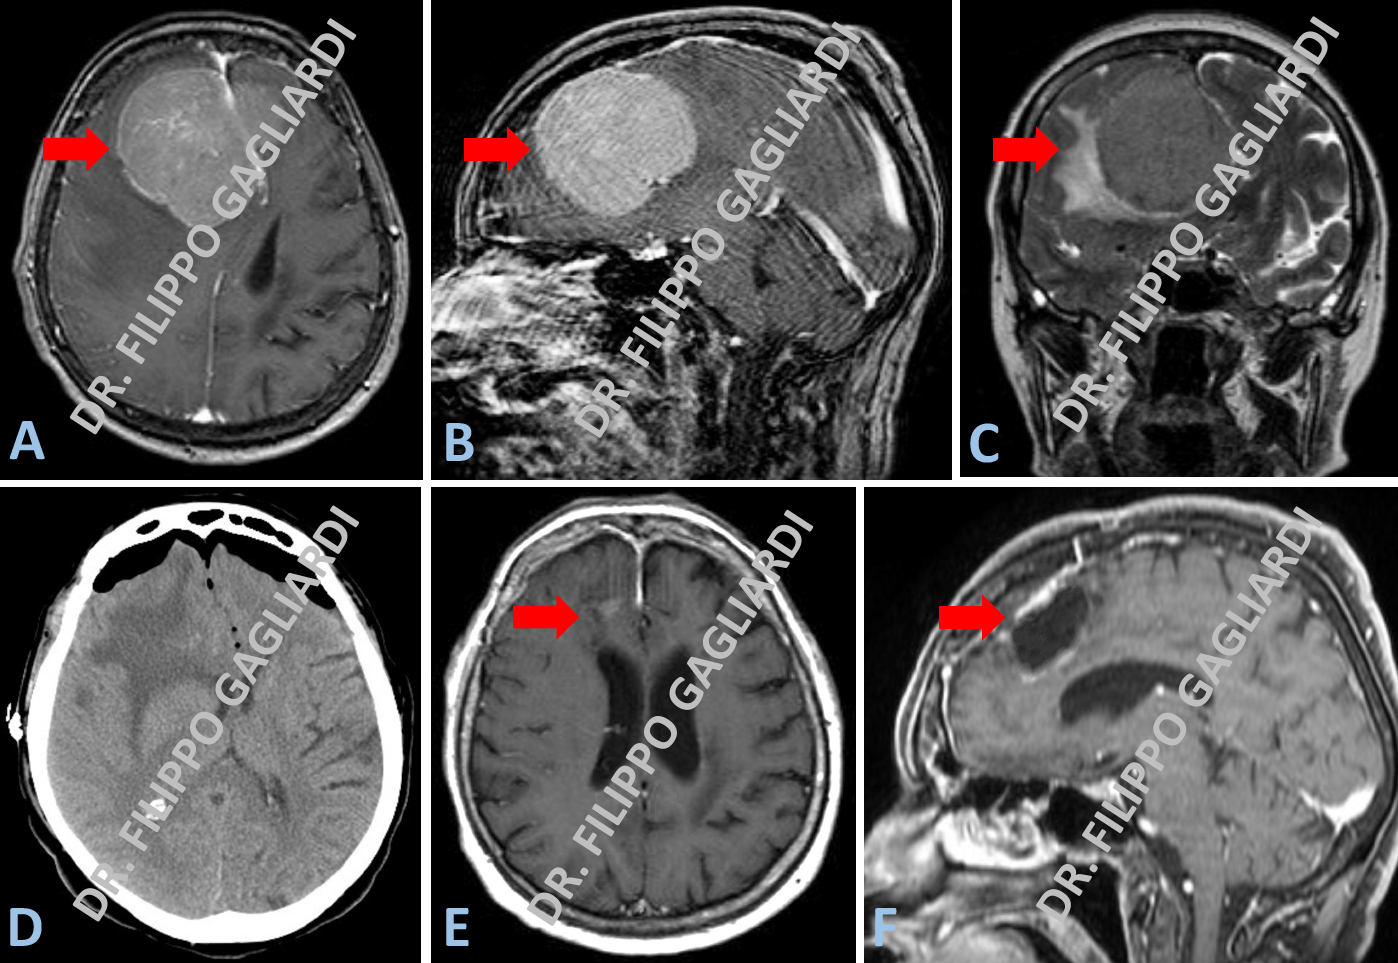

Caso di meningioma sfeno-orbitario destro (frecce azzure Figure A e B). Il tumore infiltra diffusamente il muscolo temporale (muscolo masticatorio localizzato a livello della tempia) (freccia azzurra Figura A), l’osso della volta cranica lateralmente e la parete laterale dell’orbita (freccia azzurra Figura B). La TC post-operatoria documenta l’asportazione completa del meningioma con la decompressione dell’occhio destro e la ricostruzione del profilo del cranio e dell’orbita con una mesh (rete) in titanio (frecce rosse Figura C).